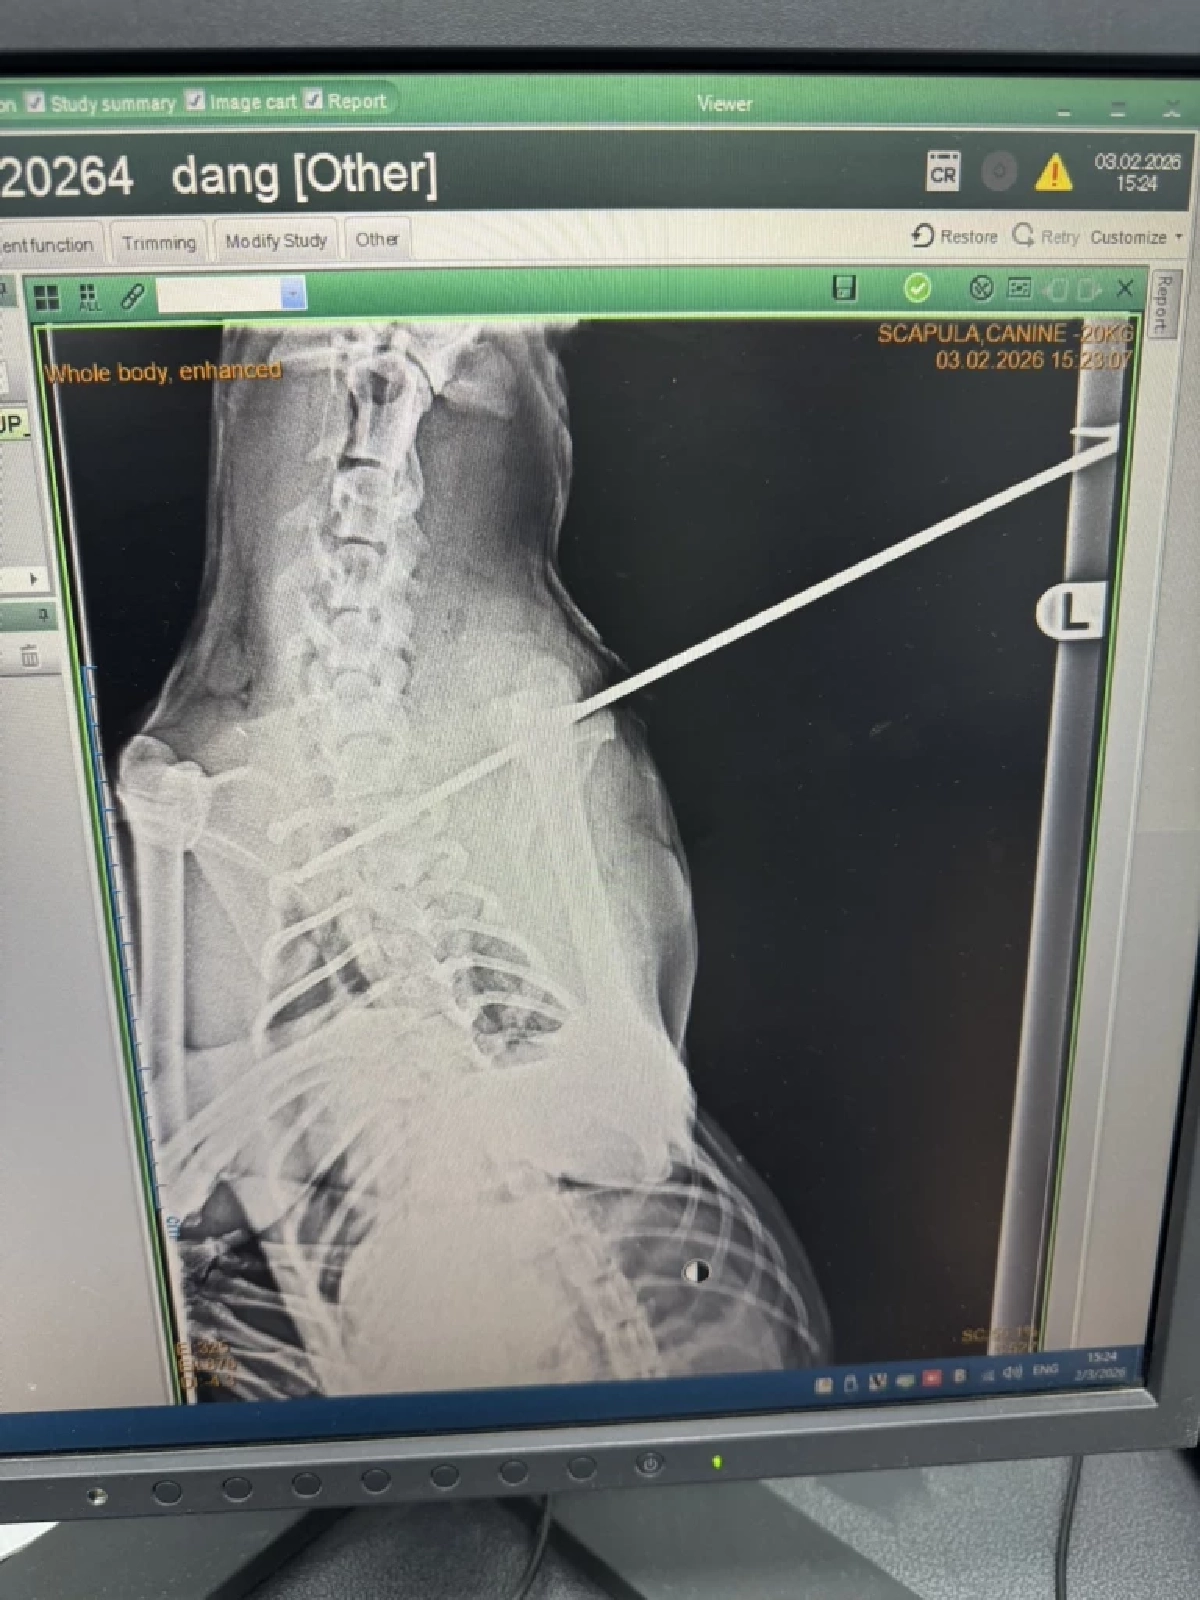

ผู้สื่อข่าวรายงาน 3 ก.พ. 2569 เจ้าหน้าที่กลุ่มจิตอาสาร่วมใจบึงสามพัน รับแจ้งจากหนุ่มไปรษณีย์ ว่าพบสุนัขสีน้ำตาล ถูกคนใจร้ายจับยัดใส่ถุงปุ๋ยทิ้งข้างทาง อีกทั้งยังถูกยิงด้วยลูกดอกยิงปักคาช่วงต้นขาหน้าทะลุเกือบถึงคอ ร้องโหยหวนด้วยความเจ็บปวด อยู่ในป่าไผ่ข้างทาง ในพื้นที่หมู่ที่ 17 ต.บึงสามพัน อ.บึงสามพัน จ.เพชรบูรณ์ จึงรีบออกไปให้การช่วยเหลือและสำส่งสัตวแพทย์

จากการสอบถาม นายเธียรชัย แซมเพ็ชร อายุ 29 ปี บุรุษไปรษณีย์บึงสามพันที่ไปพบสุนัขตัวดังกล่าว เล่าว่า ระหว่างที่กำลังขี่รถส่งเอกสาร ได้ยินเสียงหมาร้องโหนหวนอยู่ในป่าไผ่ข้างทาง จึงรีบจอดรถลงไปดู และพบถุงปุ๋ยถูกมัดปากไว้ ตนจึงแกะออกดู ปรากฏว่าพบสุนัขถูกยิงด้วยลูกดอกปักอยู่ตรงขา จึงรีบโทรหาสารวัตรแขก ซึ่งเป็นเจ้าหน้าที่กลุ่มจิตอาสาร่วมใจบึงสามพัน เพื่อขอความช่วยเหลือ และให้พาไปหาหมอ